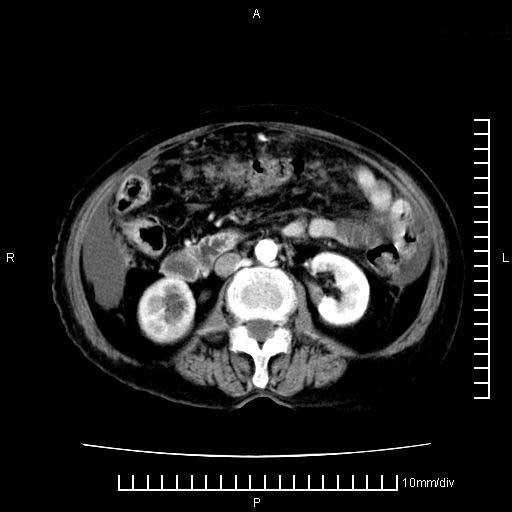

标题: CT28280:腹部增强:女性,80岁

1.胰腺颈体部癌。

4。右肾盂囊肿。

右肾盂囊肿。

3、右肾盂囊肿。

1)考虑胰腺癌并胰腺假性囊肿形成。2)肝内低密度灶,不排除转移。3)右肾盂积水。4)腹水。5)右侧胸腔积液并右肺下叶部分膨胀不全。